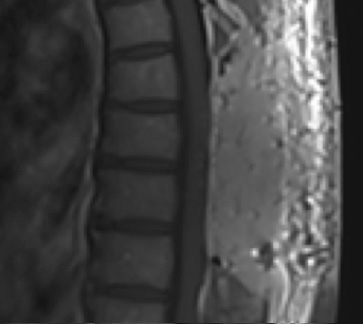

Pathology came back as Atypical Meningioma, WHO grade 2. Postoperative MRI showed a gross total resection without residual tumor, and appropriate spinal cord re-expansion. On her most recent follow-up at 6 weeks, she was very pleased with the results from the surgery. She reports resolution of her preoperative thoracic back and radicular pain, and great improvement with her ability to ambulate and overall function. It is demonstrated by her interval VAS of 2/10, and ODI of 23/100. She is expected to continue improving with time and therapy. Follow-up plan is to observe with radiographic surveillance.

Postoperative MRI T1w demonstrating a gross total resection